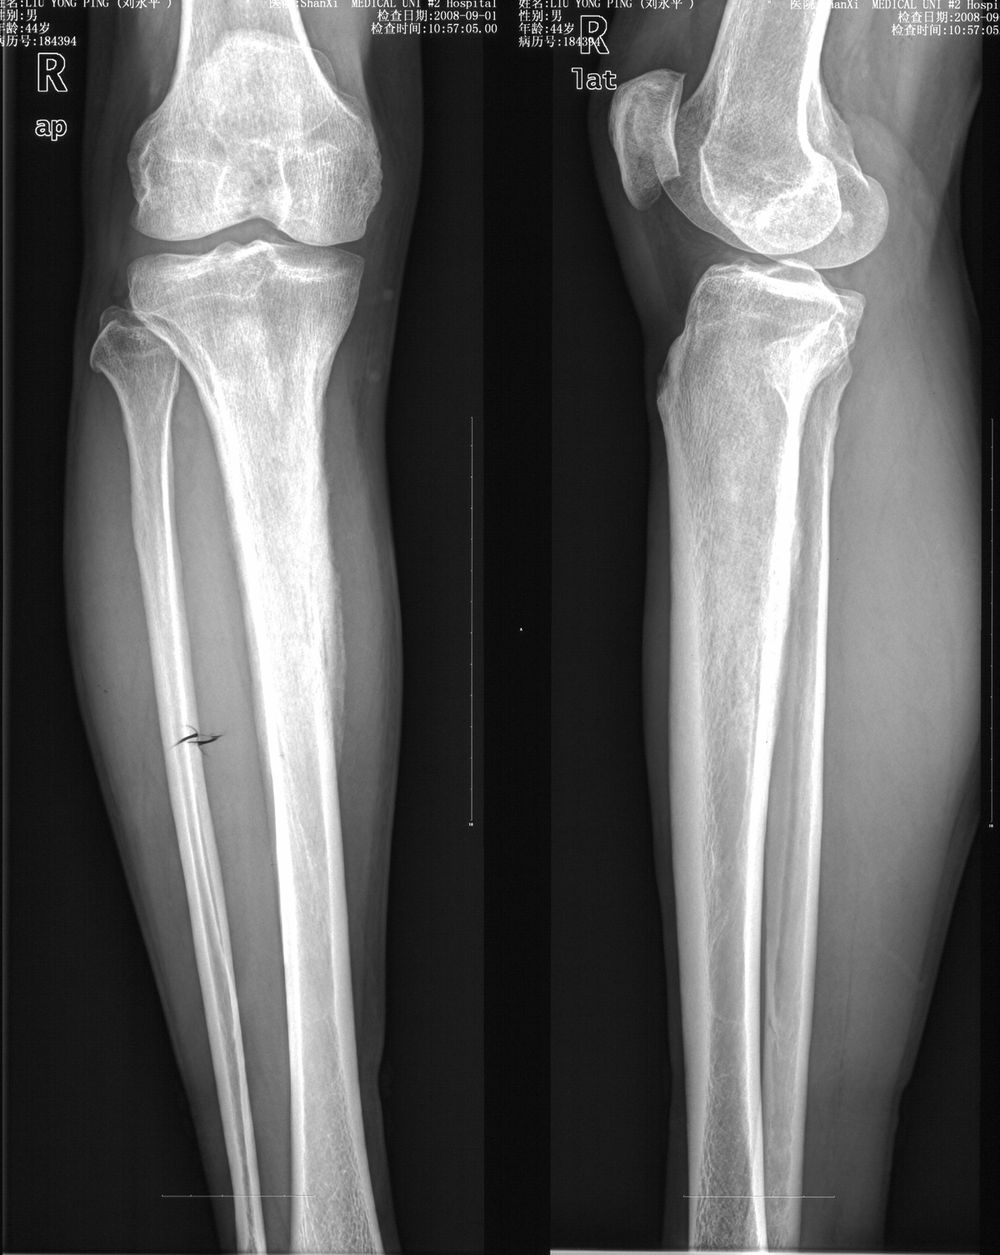

男,42岁。4个月前钢筋钝伤右侧小腿部,当时因无明显外伤,未引起重视。一周后因受伤腿部疼痛,发现肿胀,随后到当地医院进行检查(2008年4月16日)。因未发现骨质异常未引起重视,仅仅进行口服抗生素治疗处理。经过一段时间治疗但未见明显治疗效果在5月29日又进行x线检查,发现有胫骨密度上段密度增高,又进行抗炎治疗,仍未见效果。又在7月3日进行x线检查,仍然报告有胫骨上端密度增高,并建议ct检查。以下是相关检查结果:

髓腔密度呈絮状增高,胫骨上端内侧可见层状骨膜反应,考虑骨髓炎.

髓腔密度呈絮状增高,胫骨上端内侧可见层状骨膜反应,肌间隙模糊,考虑骨髓炎.

破坏、增生、骨膜反应,考虑骨髓炎

该患者到某三级医院进行会诊,并重新作了平片检查,认为畸形性行骨炎: